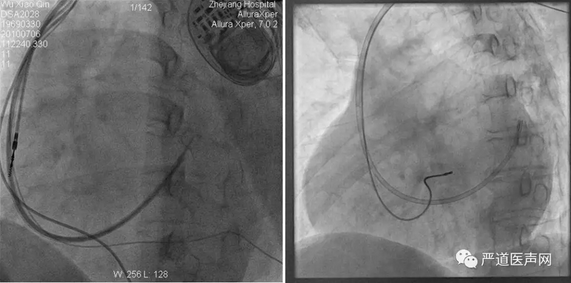

寻找CS开口方案一:传统方法

● 使用冠状窦电生理标测电极和左室递送系统一起寻找冠状窦口,常用在LAO下,以三尖瓣和脊柱作为标记来进行

LAO

寻找CS开口方案二:Amplaz导管+超滑导丝

● 借助Amplatz导管的形状和支撑,泥鳅导丝探索,推送外鞘管进入CS时注意同轴性